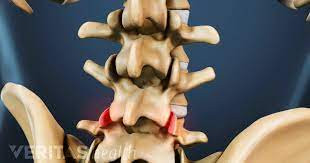

Kondisi peradangan serta kerusakan pada OA dapat memengaruhi seluruh bagian sendi.

Ruang sendi terbentuk dari struktur dua tulang dan tulang rawan di antara kedua tulang tersebut. Tulang rawan sendi ini adalah jaringan yang padat dan licin serta berfungsi sebagai bantalan kedua ujung tulang. Adanya struktur ini akan memungkinkan sendi bergerak dengan gesekan antar tulang yang sangat minimal.

OA disebabkan oleh kerusakan tulang rawan sendi yang berada di antara ujung dua tulang. Seiring penuaan dan pemakaian sendi yang terus-menerus, tulang rawan ini akan rusak, membuat ujung kedua tulang pada ruang sendi mudah bergesek ketika sendi tersebut digunakan. Selain kerusakan tulang rawan, OA juga dapat memengaruhi seluruh bagian sendi, menimbulkan kerusakan ligamen serta tendon.